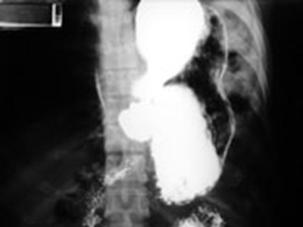

Ruptura de hemidiafragm stang cu hernierea Ruptura de hemidiafragm stang cu hernierea

stomacului si splinei stomacului si splinei.Imagine CT

Ruptura de

hemidiafragm stang cu hernierea   Ruptura de diafragm

stomacului si splinei Radiografie cu substanta de contrast

Ruptura de diafragm Ruptura de diafragm. Gastrotorax

Ruptura de diafragm. Gastrotorax Imagine CT